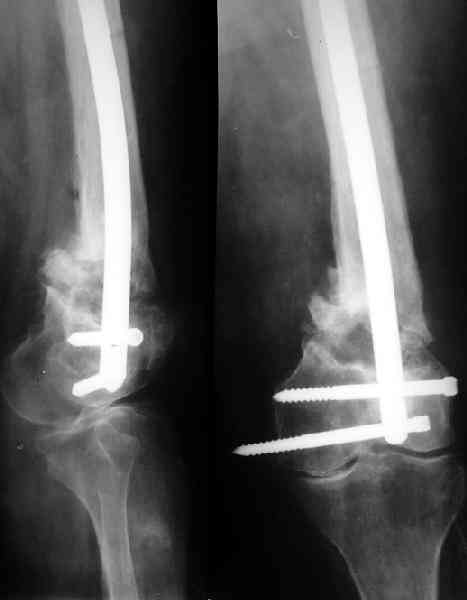

Что касается самого оперативного лечения, то оно представляет значительные трудности и положительный исход его не столь очевиден. С моей точки зрения, адекватная фиксация любой металлоконструкции в дистальном отломке бедренной кости невозможна. Поэтому вариантов вмешательства два: либо ВКДО с фиксацией голени (что, учитывая конституцию больной и сопутствующую патологию, менее приемлемо), либо антеградный БИОС с прохождением стержня через коленный сустав и дистальным блокированием в проксимальном эпиметафизе большеберцовой кости. И в том и другом случае потребуется открытая репозиция и костная пластика (возможно в несколько этапов). Вопросы восстановления длины конечности и функции коленного сустава на данном этапе лечения не главные. Цель оперативного лечения – восстановление опорной функции конечности и сращение перелома.

Пример подобного ложного сустава в приложении.

На сегодня есть имплантаты с куда более продвинутой дистальной фиксацией.

Да практически у всех производителей есть сегодня бедренные стержни с возмоностью ввести винты максимально дистально, и более 2. Это и Synthes, и Stryker, и DePuy, и ChM, и даже предприятие "ЦИТО". Единственное - диаметр винтов. Желательно больше 5 мм.

Спасибо. Прооперировали во вторник.

Выглядит красиво. А движения в колене какие были на столе?

Была контрактура и спаянный с суставной поверхностью надколенник. Сделали до синтеза редрессацию. Достигли почти полного объема движений.